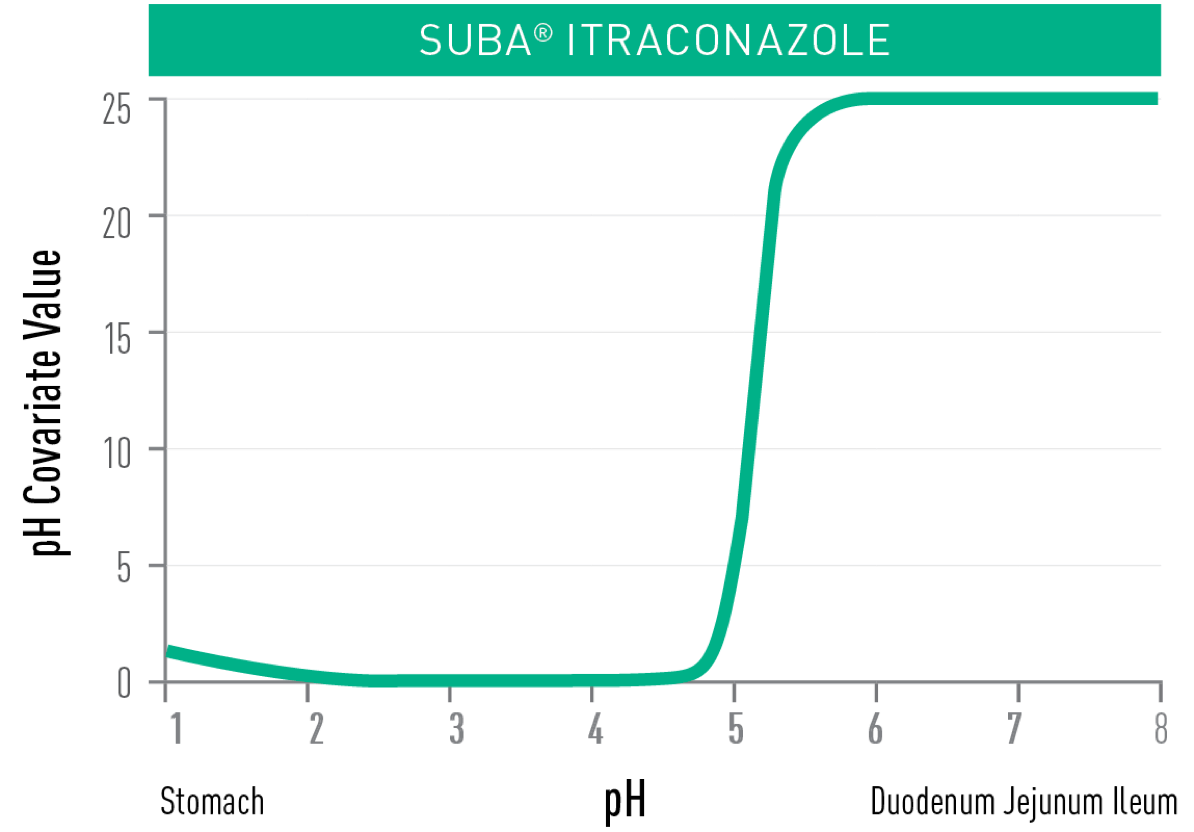

UNLIKE CONVENTIONAL ITRACONAZOLE,

TOLSURA is less soluble in the acidic environment of the stomach and soluble in the higher pH of the small intestine, resulting in improved absorption2.

- THE ABSORPTION OF TOLSURA IS NOT REDUCED† with proton pump inhibitors as the

drug is released in the small intestine5,7,8.

†Monitor for side effects as dosing with a proton pump inhibitor may increase peak and overall exposure of itraconazole